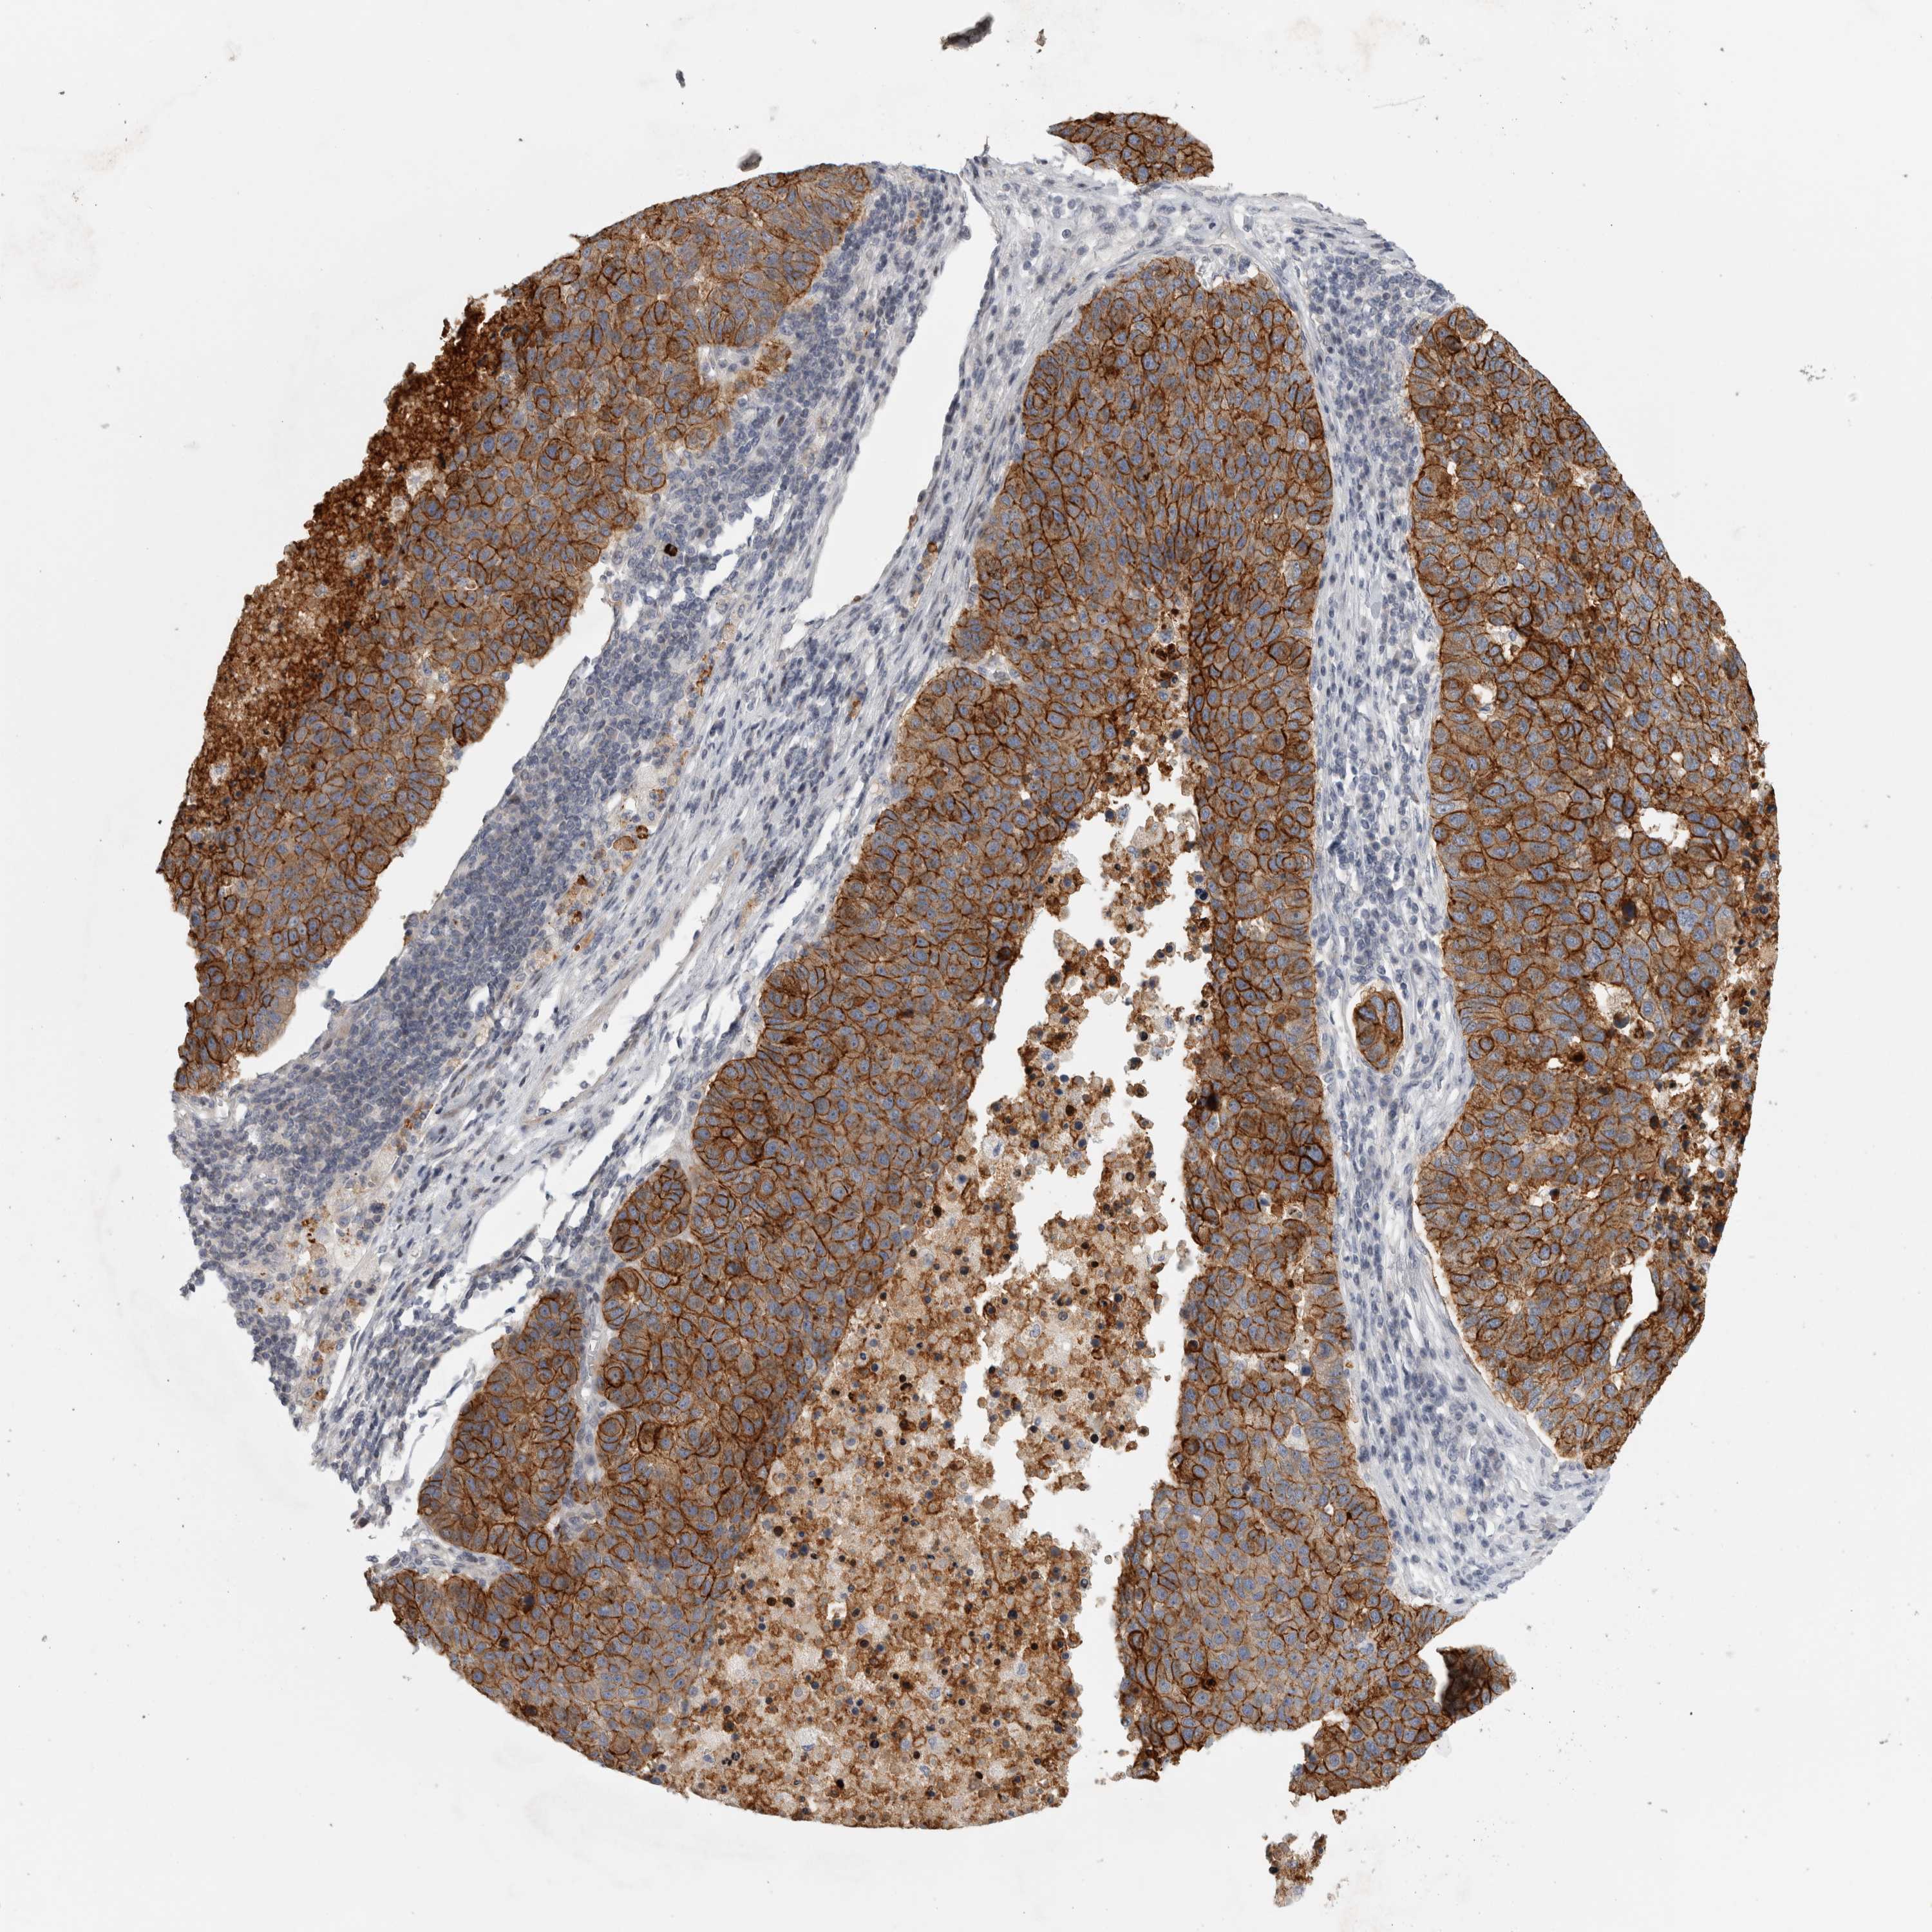

PANCREATIC CANCER - Protein expressioni

A mouse-over function shows sample information and annotation data. Click on an image to view it in a full screen mode. Samples can be filtered based on level of antibody staining by selecting one or several of the following categories: high, medium, low and not detected. The assay and annotation is described here.

Note that samples used for immunohistochemistry by the Human Protein Atlas do not correspond to samples in the TCGA dataset.

Antibody stainingi

Antibody staining in the annotated cell types in the current human tissue is reported as not detected, low, medium, or high, based on conventional immunohistochemistry profiling in selected tissues. This score is based on the combination of the staining intensity and fraction of stained cells.

Each image is clickable and will lead to virtual microscopy that enables deeper exploration of all samples and also displays staining intensity scores, fraction scores and subcellular localization as well as patient and tissue information for each sample.

Antibody HPA026640

Staining

High

Medium

Low

Not detected

Intensity

Strong

Moderate

Weak

Negative

Quantity

>75%

75%-25%

<25%

None

Location

Nuclear

Cytoplasmic/membranous

Cytoplasmic/membranous,nuclear

Adenocarcinoma, NOS

Adenocarcinoma, metastatic, NOS